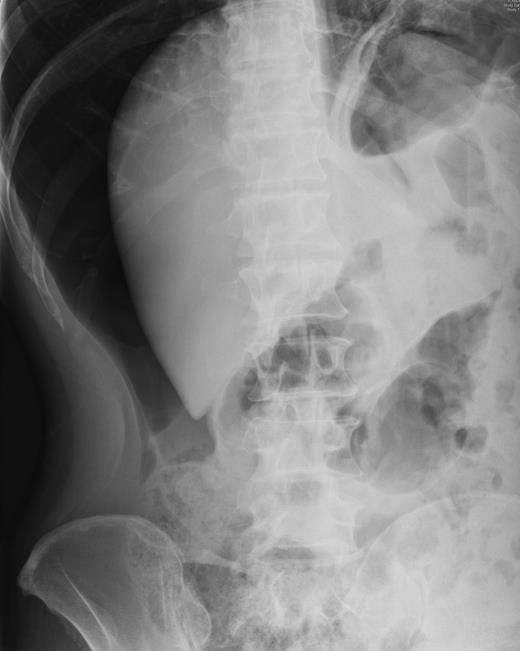

Over a year later, the same gentlemen presented to the surgical admissions unit once again with a history of acute abdominal pain. The duration and nature of symptoms were very similar to his previous admission. He again underwent plain film abdomen and erect chest radiographs that showed a large volume of free air under the diaphragm (Figs. 4 and 5).